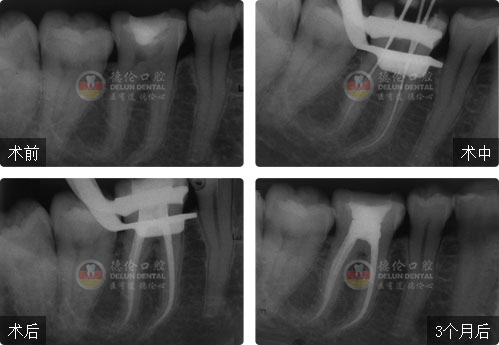

刘阗主任全国根管治疗技术竞赛获奖案例展示

显微根管技术 让牙痛更快速的消除

根管治疗俗称“杜牙根”或“杀神经”,由于龋齿、外伤等原因导致牙髓组织感染引发牙齿疼痛,根管治疗就是将感染的牙髓组织清理干净再填充上药物,使牙痛得到有效治疗。

刘 阗主任医师

省级现代根管治疗继续教育项目讲师

德伦口腔集团牙体牙髓技术总监兼总院全科主任

全国根管治疗技术竞赛二等奖获得者

擅长项目:成人牙体牙髓病、儿童牙病及牙外伤的诊断与治疗,显微镜下根管治疗技术、前牙美学修复。